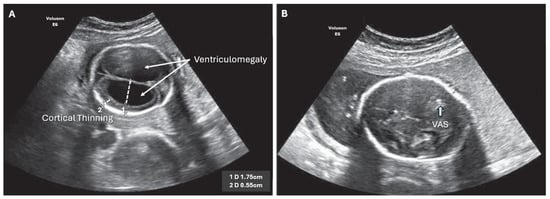

Figure 1. Imaging in the transventricular plane of ISVM at 22.3 weeks of pregnancy: (A) transabdominal ultrasound: the atrial width of the distal ventricle is increased at AD = 19.1 mm, and (B) MRI of T2-dependent sequence SSFSE.

Figure 2. ISVM fetal ultrasound before (A,B) after VAS implantation, arrow indicates VAS.

Sonographic evaluation remains the imaging test of choice due to its ease of application, test repeatability, low cost, and availability of the equipment at fetal medicine centers []. The standardized AD should be measured in the transventricular plane (axial) at the level that demonstrates the frontal horns and cavum septi pellucidi, in which the appearance of the hemispheres is symmetrical []. The caliper should be placed on the interior margin of the medial and lateral wall of the atria, at the level of parietal-occipital groove and glomus of the choroid plexus, on the axis that is perpendicular to the long axis of the left ventricle (Figure 1 and Figure 2). The measurements are perpendicular to the long axis of the left ventricle. In the case of fetal VM, the choroid plexus appears to be ‘dangling’ or falling towards the dependent ventricular wall and occupies less space in the ventricle than in cases without VM []. In cases without VM, the choroid plexus typically takes up at least half or more of the lateral ventricle []. Asymmetric VM is defined in the second trimester of pregnancy as an AD difference of >2 mm, with one or both ventricles larger than >10 mm []. Unilateral dilation of the ventricles is reported for 50–60% of the cases []. Patients with unilateral VM have similar neurodevelopmental outcomes as those with bilateral VM []. Agenesis of the corpus collosum (ACC), which is caused by the blockage of that structure by the dilated VM, is often observed in INSVM as well as ISVM. Color Doppler ultrasound is useful when searching for the periventricular aorta to confirm complete or partial agenesis of the corpus collosum [].

Isolated non-severe ventriculomegaly (INSVM) is diagnosed on ultrasound for an AD of >10–14.9 mm and in the absence of other associated cranial and non-cranial malformations, together with the echocardiography of the fetal heart [,]. As further diagnostic procedures are necessary, INSVM is the diagnosis of only the ‘apparent’ malformation [,]. The parents should be informed that it is merely a preliminary diagnosis, and that, in 13% of the cases, it is initially not possible to identify other serious cerebral defects. Further observation using repeated ultrasound testing is necessary as the AD value does not have a uniform model of evolution: stability—55%, regression—30%, and progression to the AD ≥ 15 mm in 16% of the cases [,]. Perlman et al. compared prenatal and postnatal imaging in a cohort of 92 INSVM fetuses (AD ≥ 10–<14 mm) and found statistically significant regression of the prenatal isolated ventriculomegaly (p < 001). During clinical follow-up at 24 months, normal development was observed in all infants except three, who presented with very mild neurological deficits [].

Isolated severe ventriculomegaly (ISVM) is diagnosed on ultrasound for an AD of ≥15 mm []. Third ventricle imaging on the sagittal plane using 3D transvaginal neurosonography is the new measurement point for ISVM due to the fact that it reveals a strong correlation between the interthalamic adhesion diameter and postnatal diagnosis of aqueductal stenosis (98.6% accuracy, CI 0.92–0.99) [,]. Brinbaun et al. reported that transvaginal neurosonography allows visualization of the normal and abnormal third ventricle of the fetus. An ITAD < 7.1 identifies aqueductal stenosis as the likely etiology of severe ventriculomegaly with 98.6% accuracy [].